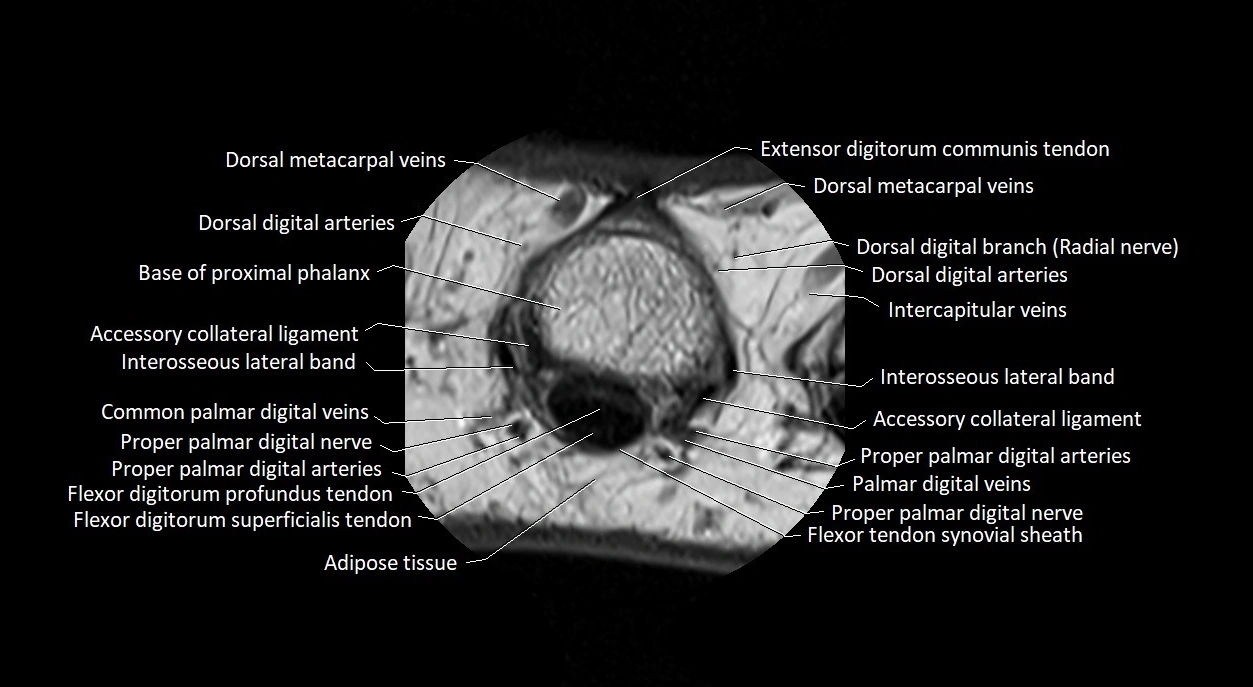

MRI images

image